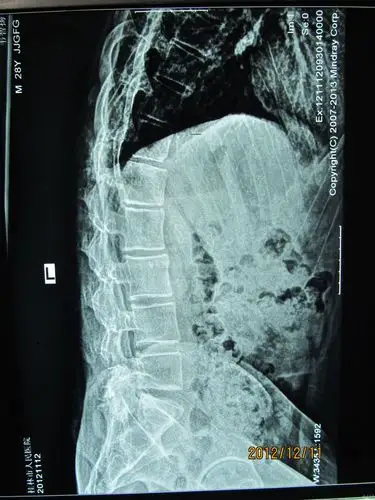

强直性脊柱炎方形椎

强直性腰椎脊柱炎x线照片.美联社的观点.